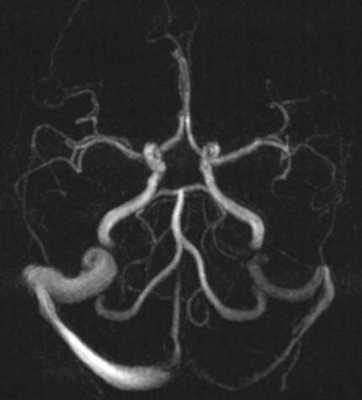

Исключали клинически значимую кардиологическую и лёгочную патологию. Обработку полученных данных проводили при помощи пакета статистических программ SPSS 10 с использованием критериев Стьюдента и Манна - Уитни. Результаты и их обсуждение. Учёт венозной фазы кровотока при МРТ-реконструкции сосудов головного мозга позволил верифицировать варианты развития поперечного и сигмовидного венозных синусов в виде их гипоплазии (рис.1) и полной аплазии (рис. 2).

Рис. 1. МРТ-визуализация сосудов головного мозга с венозной фазой мозгового кровотока. Гипоплазия левого сигмовидного и поперечного венозных синусов головного мозга. Существенное снижение кровотока в левых сигмовидном и поперечном синусах. Асимметрия кровотока в яремных венах - 86 и 14 %

Рис. 2. МРТ-визуализация сосудов головного мозга с венозной фазой мозгового кровотока. Отсутствует кровоток в левых сигмовидном и поперечном синусах. Асимметрия кровотока в яремных венах - 98 и 2 % (аплазия синусов)